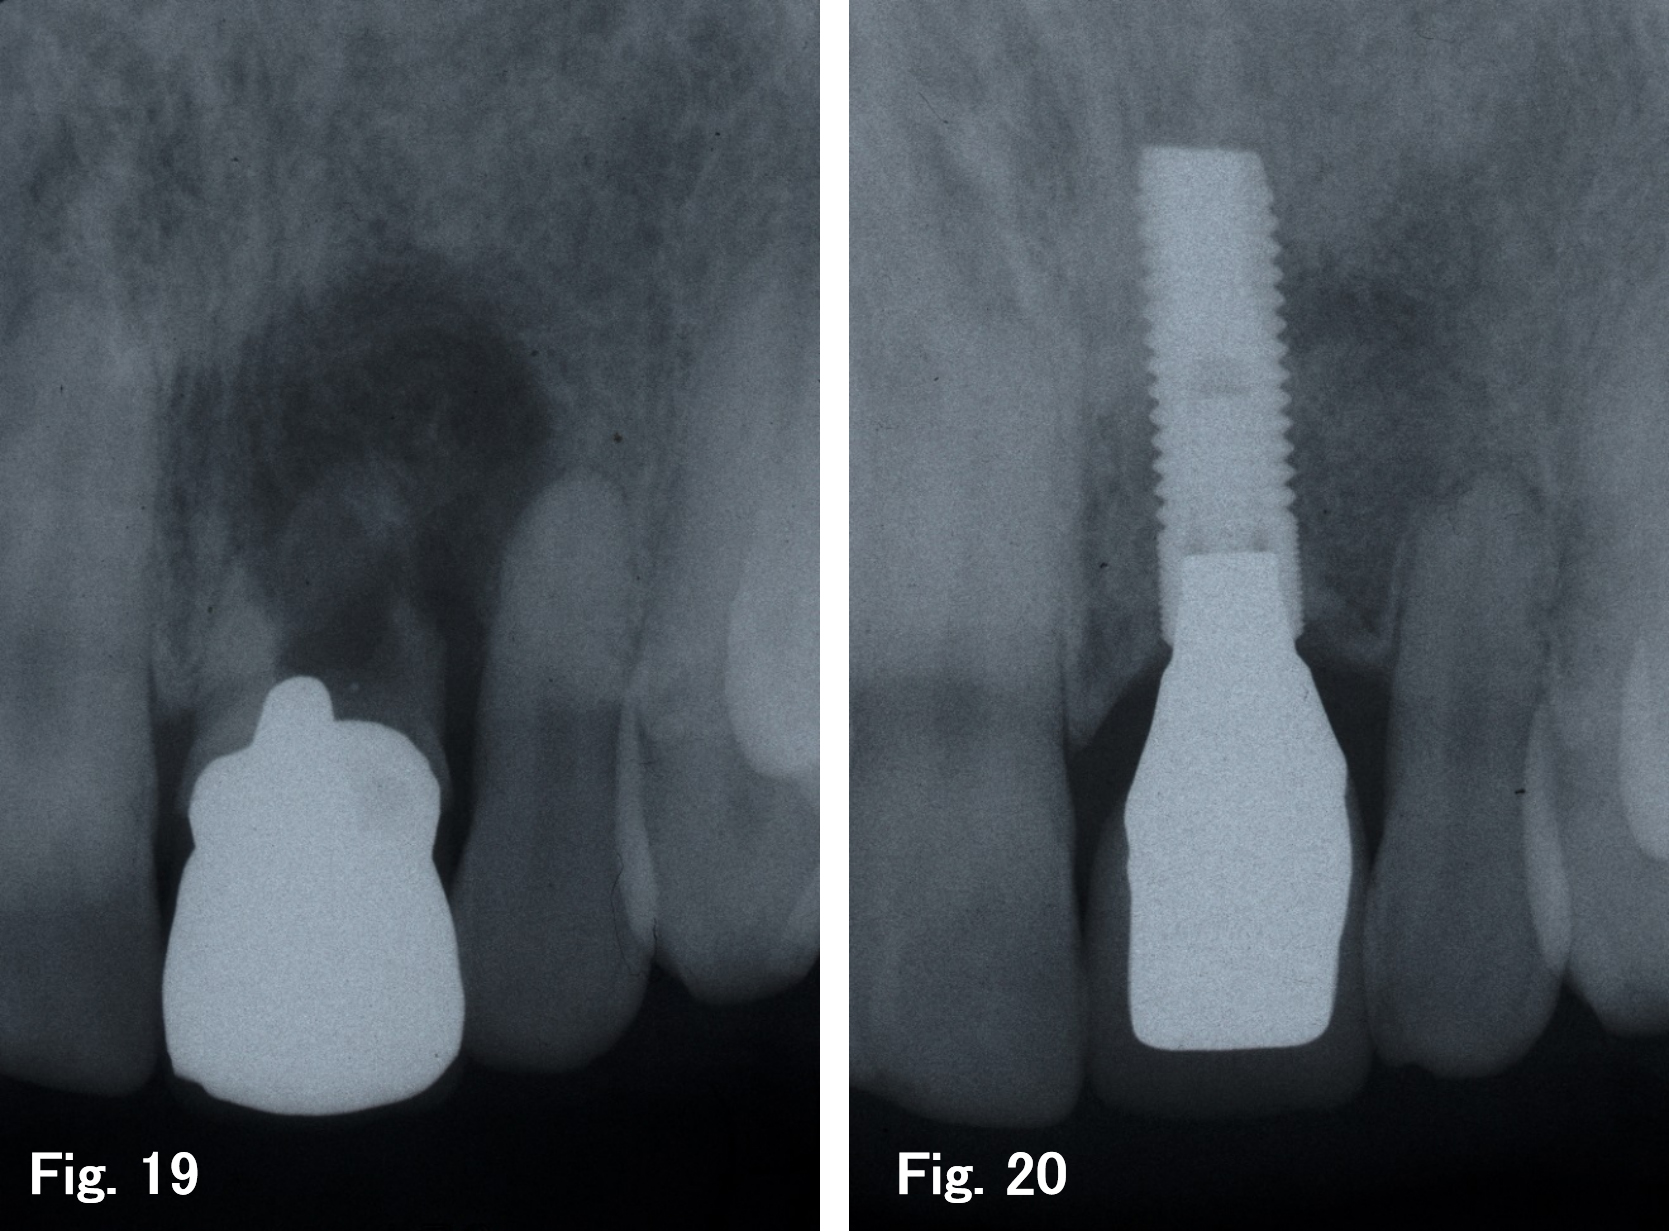

某歯科医院より前歯の治療を依頼された(Fig.1)。患歯は破折して久しく、著しい骨吸収(Fig.19)が見られたため、抜歯即時インプラントの適応にはならない。注意深く抜歯を行ったところ、唇側の骨はなく(Fig.2)、嚢胞を摘出すると大きな骨欠損が認められた(Fig.3)。抜歯後3ヵ月程度の治癒期間を経て(Fig.4)、インプラント埋入を行ったが、骨欠損が大きく、審美的な障害が懸念されたため(Figs.5,6)、骨増生を併用した(Figs.7,8,9)。再び埋入後6ヶ月の治癒期間を経て(Figs.10,11,12)、2次手術を行い、設置されたゴアテックス膜下部には十分な骨増生を認めたため骨整形を行い(Figs.13,14,15)、ヒーリングアバットメントを設置した(Fig.16)。その後、通法どおり上部構造体を作製(Fig.17)し、メインテナンスに移行して、 現在3年が経過した(Fig.18)。審美的にも満足でき、また存在した骨欠損も回復し、隣在歯の歯根膜腔も回復している(Fig.20)。